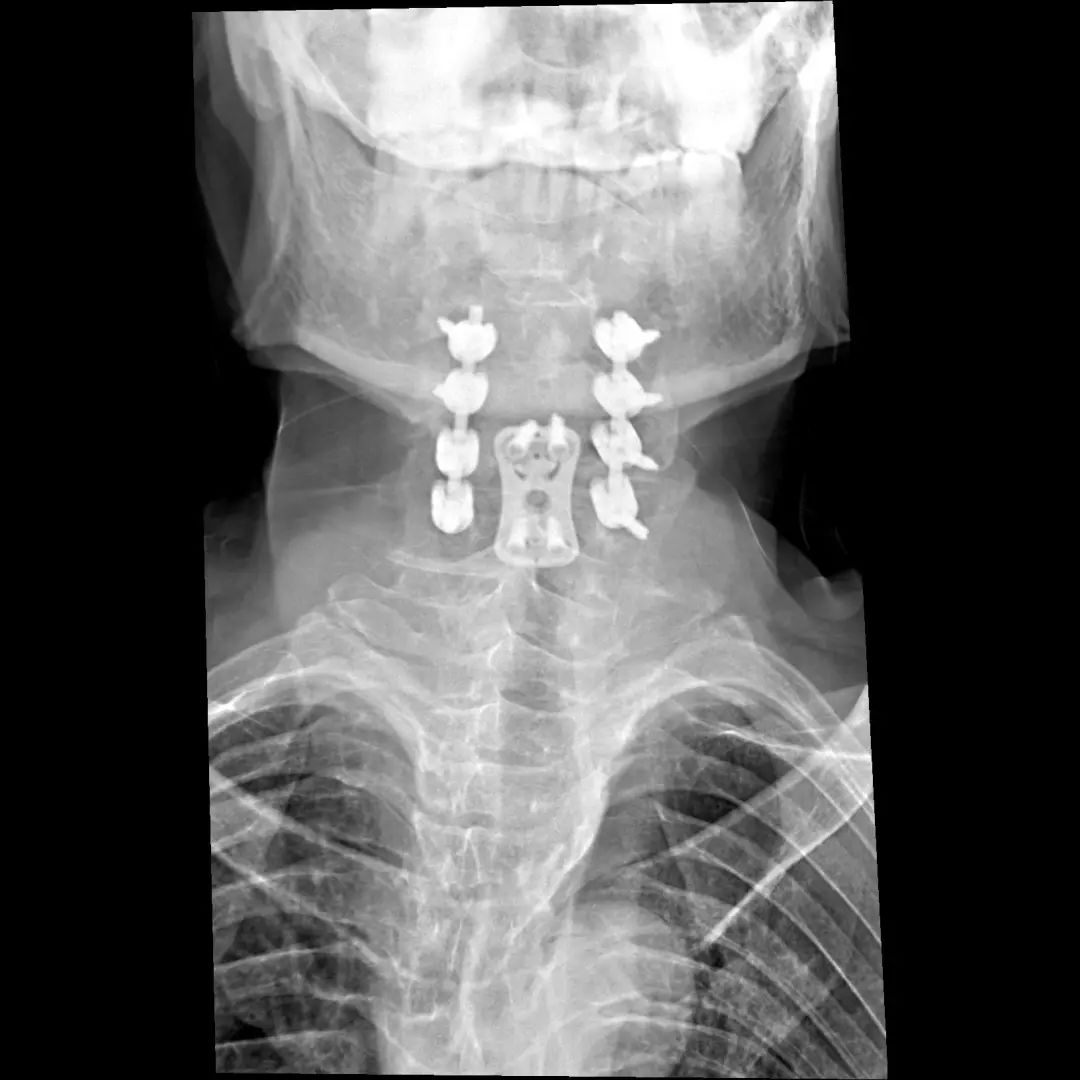

经过全程监护和系统治疗,患者术后恢复良好,骨折解剖复位,复查X线及CT显示固定位置佳,术后3天下地行走,术后4天即出院回家休养。

该手术为我市首例完成C1、2椎弓根钉棒系统固定手术,填补了枣庄在上颈椎外伤手术史上的空白,展现了枣庄市立医院脊柱外科不怕困难、勇于突破、积极向上的精神面貌,也是王存平主任技术高超、胆大心细的具体体现。